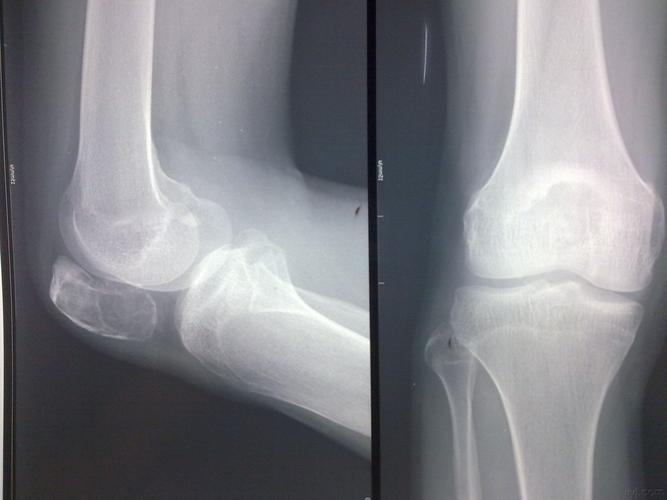

肱骨骨囊肿

骨囊肿

骨囊肿ct

动脉瘤样骨囊肿影像

动脉瘤样骨囊肿